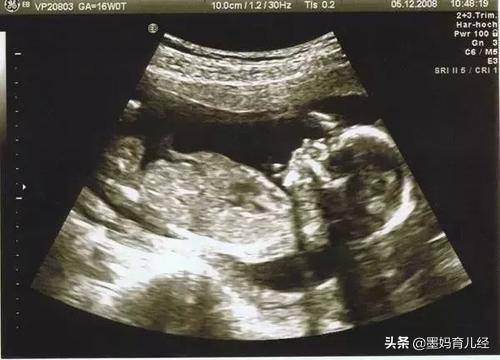

只要按时孕检才可以让我们及时掌握胎宝宝在孕妈宫内是否健康安全,而在孕检中发觉异常也可以马上得到干预,治疗,诸如胎宝宝是否氧气不足或是别的异常状况。